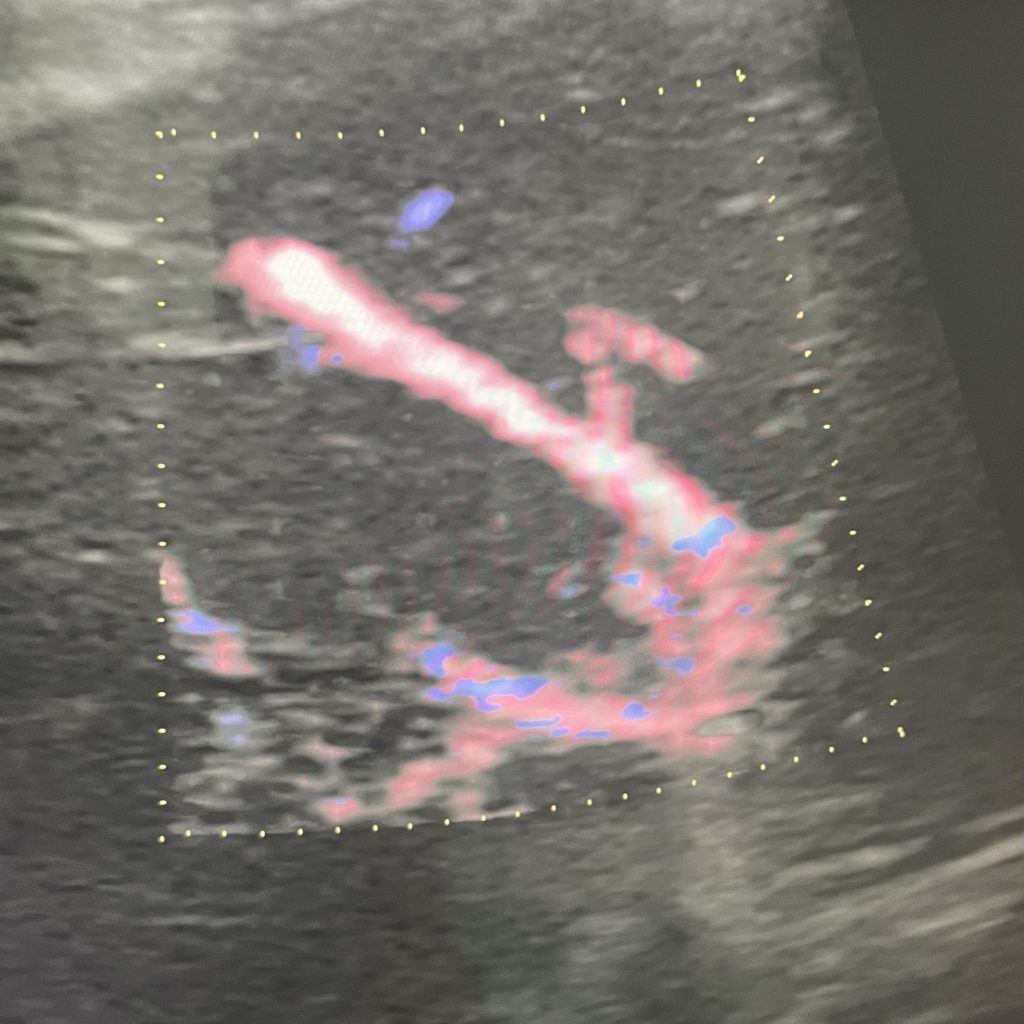

オレンジで囲まれた場所が尾状葉です。カラードップラーといって血流を見る検査で全く血流がないことがわかります。(青線は腎臓です)

近くの肝臓は・・・

このように赤と青で色がついています。これはしっかり肝静脈に血流があることを示しています。